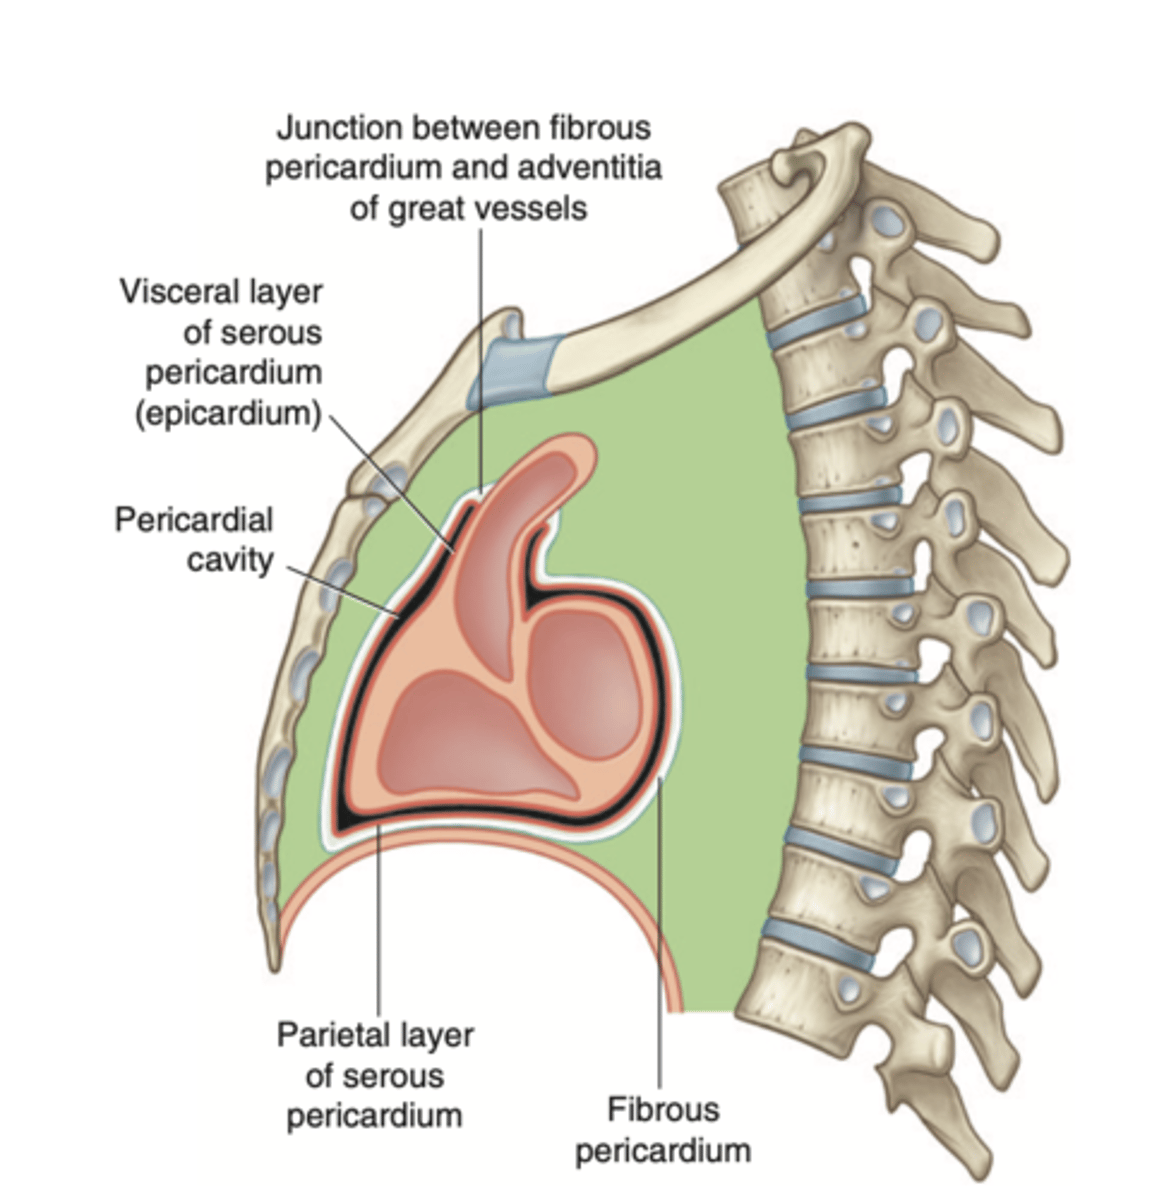

What are the layers of the pericardium?

The pericardium consists of two main layers:

- the fibrous pericardium

- the serous pericardium

How is divided the serous pericardium?

. Visceral layer or Epicardium (innermost). Adheres to the heart

. Parietal layer (outermost)

Between these layers is the pericardial fluid (pericardium cavity )

What is the fibrous pericardium?

the tough, outer layer

protects the heart

maintains its position in the thorax.

defines the boundaries of the medium mediastinum